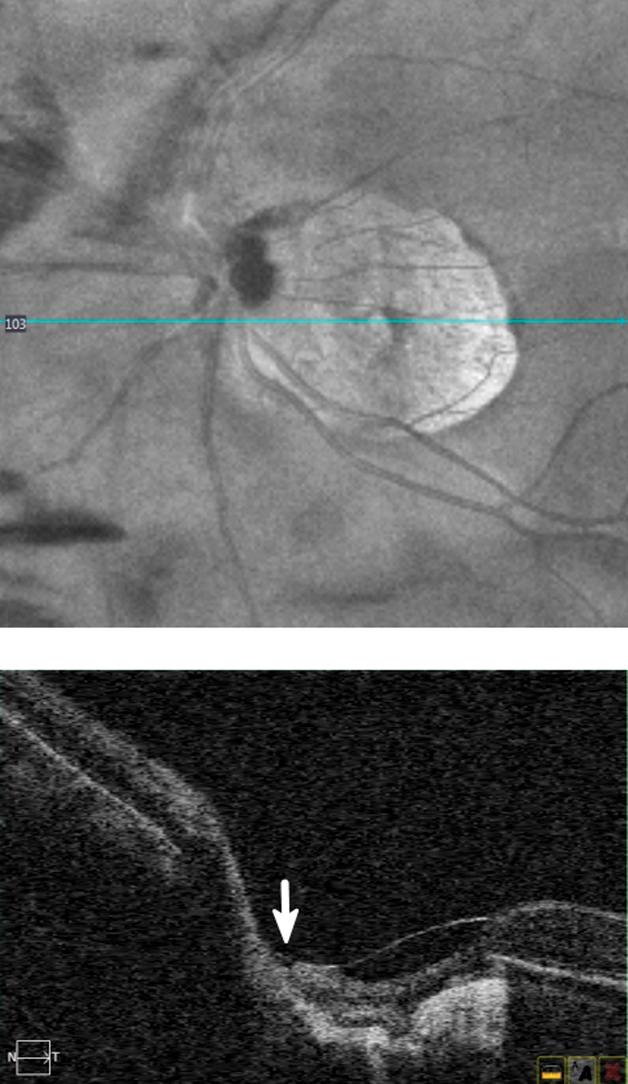

To present a case of a myopic macular hole that spontaneously closed twice in the presence of a broadly adherent posterior hyaloid membrane.

A 49-year-old man with high myopia and pseudophakia had a full-thickness macular hole in the left eye. The hole spontaneously closed in all retinal layers before the elective surgery, but the macular hole recurred one month later. The hole started sealing again spontaneously after one month, leaving a defect in the outer retinal layers. Four months later, the outer layer defect sealed and a lamellar macular hole developed. Throughout the course, the posterior hyaloid membrane remained parallel to the macular surface. The macular morphology and the patient's vision remained stationary at the 2-year follow-up.

This case demonstrated that myopic macular holes can form and seal repeatedly with a broadly adherent posterior hyaloid membrane. Although bridging phenomenon was the common sign indicating the initiation of the two hole closures, different patterns of tissue regeneration ensued.

报告一例伴有广泛后玻璃体膜粘连的近视性黄斑裂孔两次自发闭合的病例。

一名 49 岁的高度近视和人工晶状体眼患者左眼出现全层黄斑裂孔。在择期手术前,裂孔在所有视网膜层自发闭合,但一个月后黄斑裂孔再次复发。一个月后,裂孔再次开始自发封闭,仅在外层视网膜留下一个缺损。四个月后,外层缺损封闭,形成板层黄斑裂孔。整个过程中,后玻璃体膜始终与黄斑表面平行。黄斑形态和患者视力在 2 年随访时保持稳定。

本病例表明,伴有广泛后玻璃体膜粘连的近视性黄斑裂孔可以多次形成和闭合。尽管桥接现象是表明两次裂孔闭合开始的常见标志,但随后出现了不同的组织再生模式。